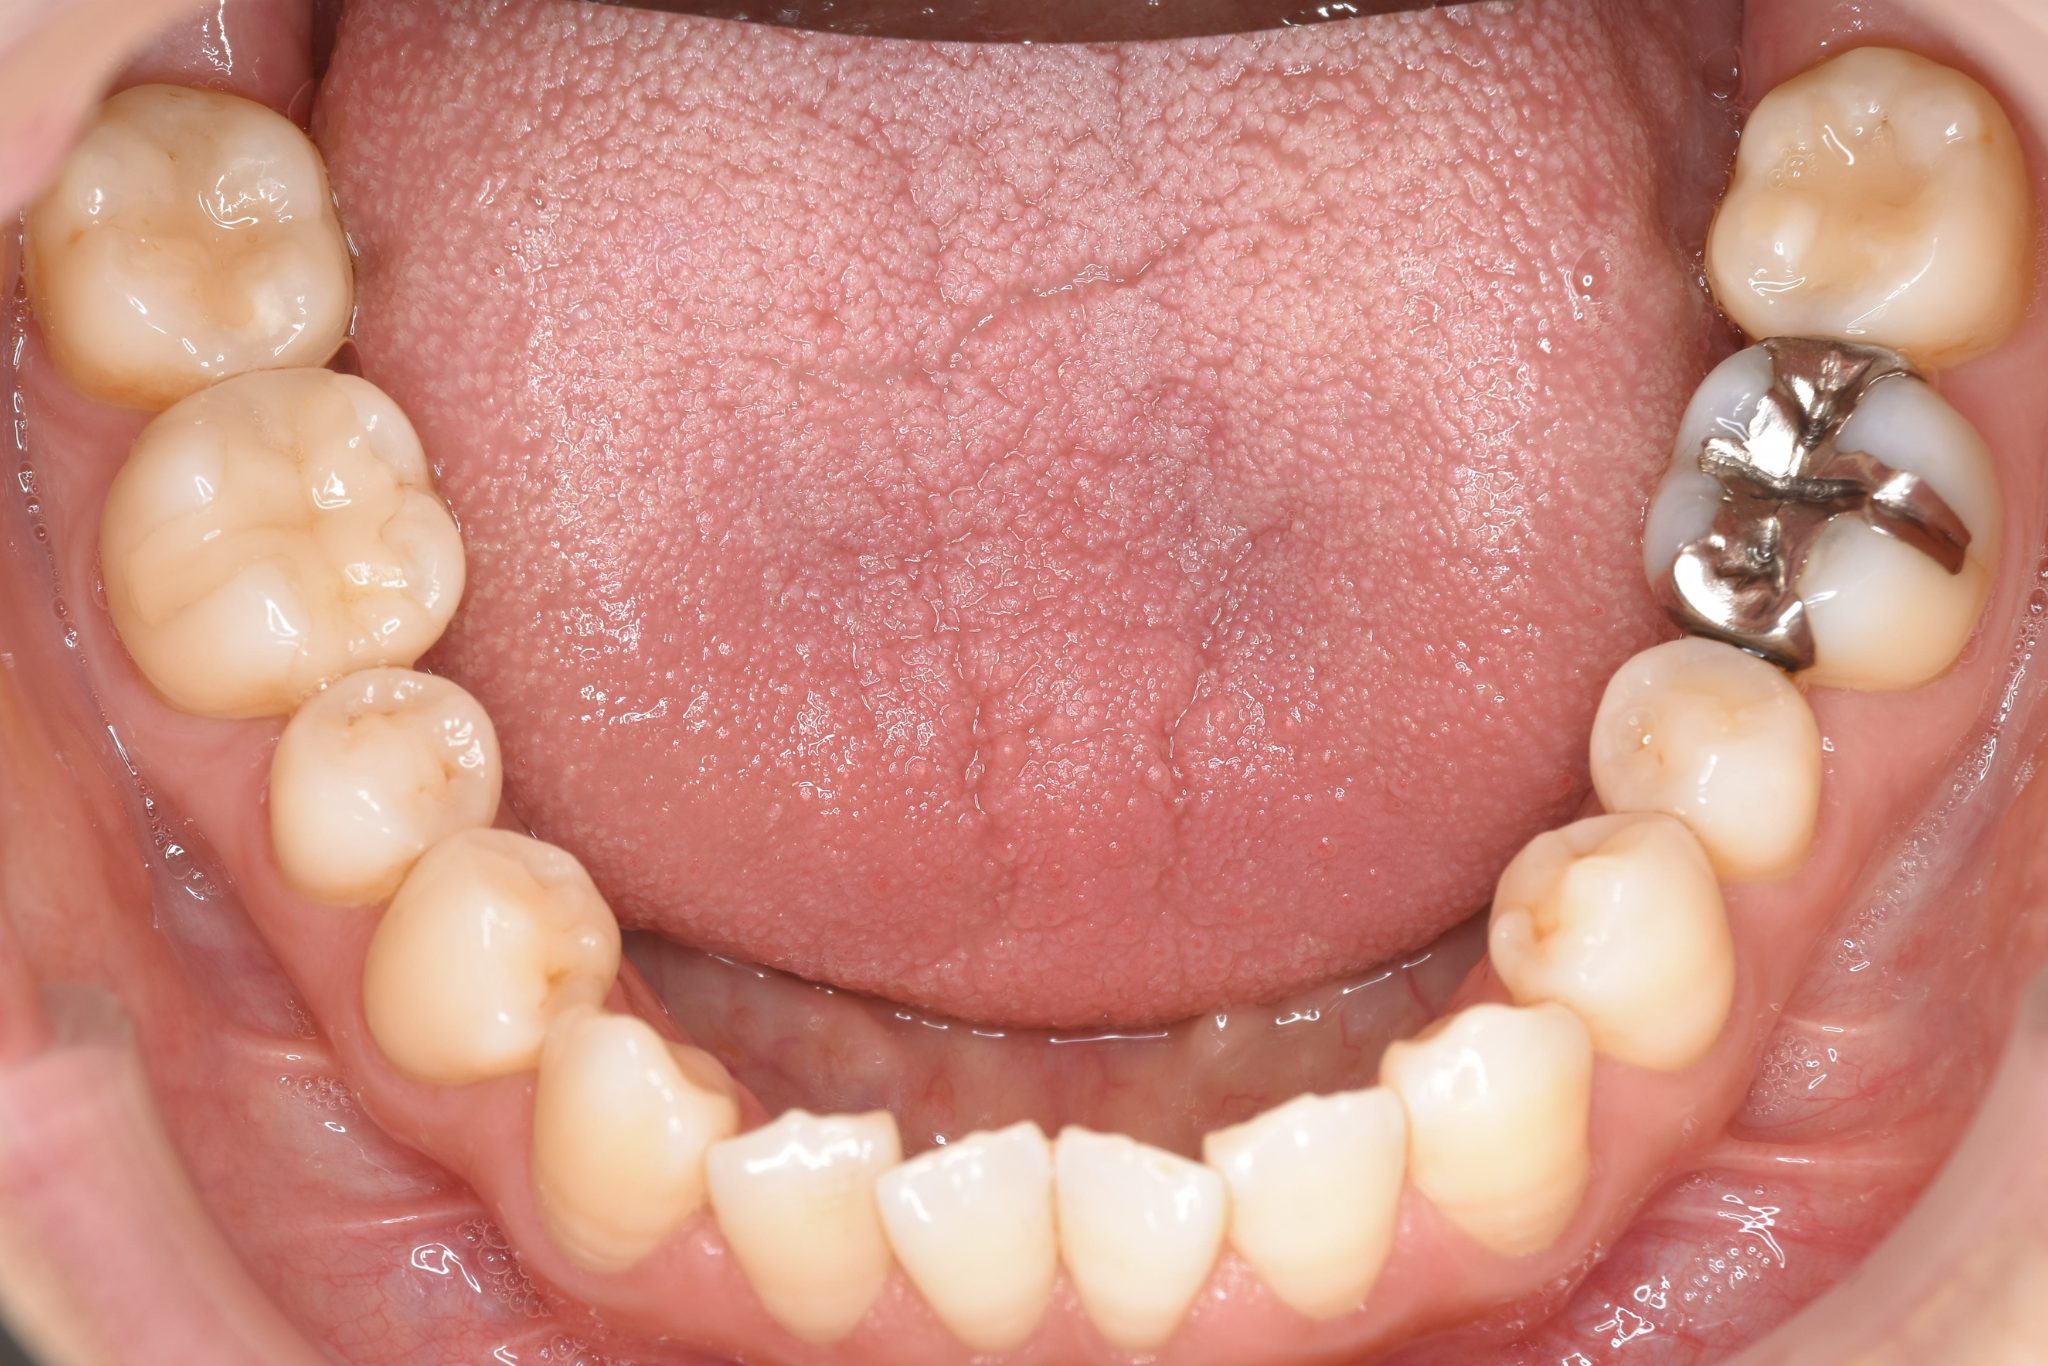

ビフォー

保険での矯正治療|症例_138